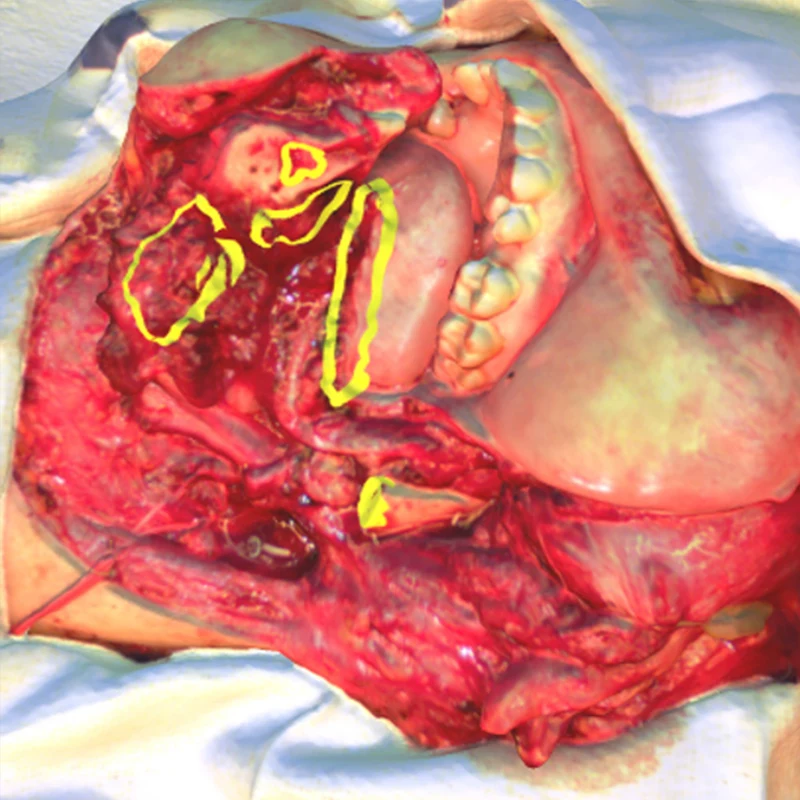

3D scanned image of a defect following a partial mandibulectomy and floor of mouth resection. Annotations indicate the precise location and breadth of supplemental margins harvested.